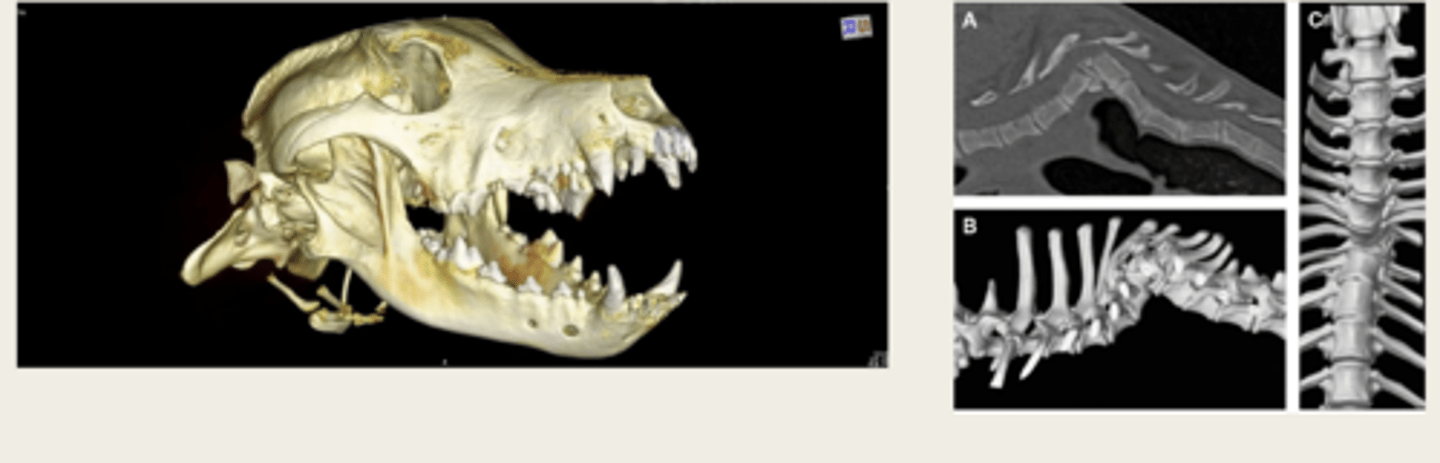

-surgical planning

-radiation therapy planning

-3D printing

CT is primarily used for diagnosing problems, but can also be used for what three other things?

CT volume rendering/3D reconstruction

what is the image on the left showing?